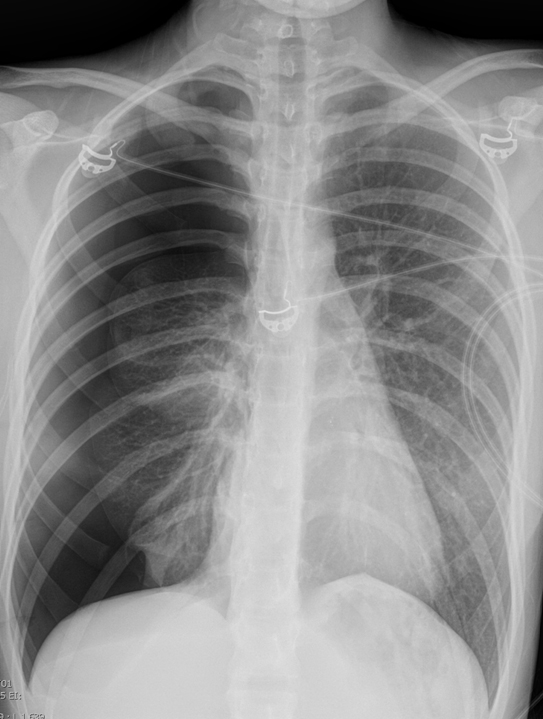

Gallery Pleural Pneumo - mild tension

Pneumo - mild tension